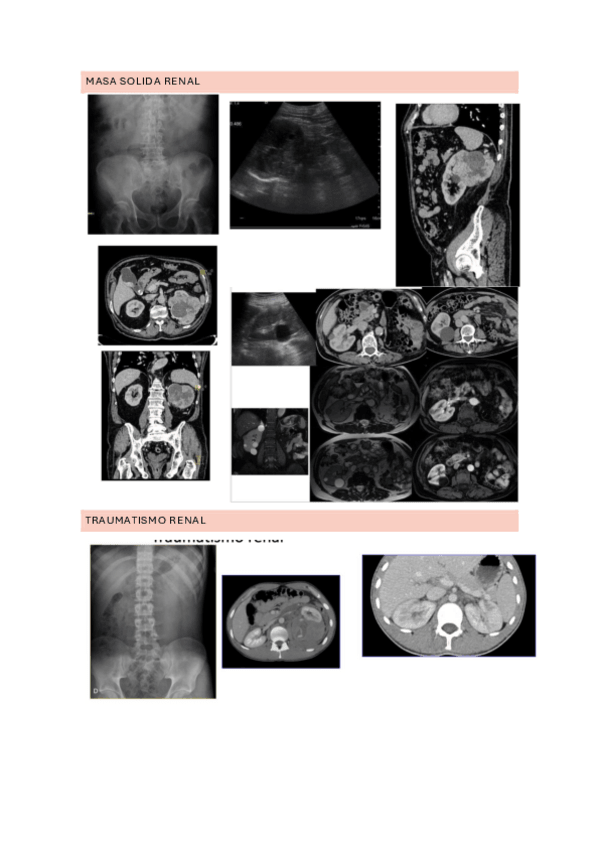

Es la parte final del tema 10.q creo que es nueva. Son prácticamente todo fotos, pero por si alguien lo quiere para imprimirlo y meterlo en sus apuntes